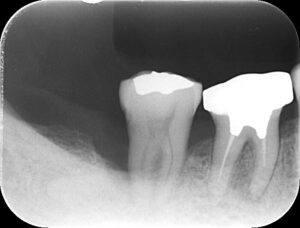

手術直後のレントゲン写真です。

歯石は取れていますが、もちろん骨は溶けたままで凹んでいます。

半年後のレントゲン写真をお見せします。

いかがでしょうか。

骨が元の位置まで戻っているとは言えませんが、

凹んでいた部分はなくなっています。

つまり、骨は一部再生したのです。

もう一度、治療の前後で比較してみましょう。

治療前

治療後

骨が再生しているのがわかります。

ただし、健全な状態まで骨が回復したとは言えません。

歯の長さの半分くらいまでしか骨がないので、

歯周病により骨が吸収してしまった状態であることは変わっていません。

ですが、治療前と比べて、

局所的に骨が溶けている部分はなくなり、

骨のラインがなだらかに、そしてはっきり見えるようになっています。